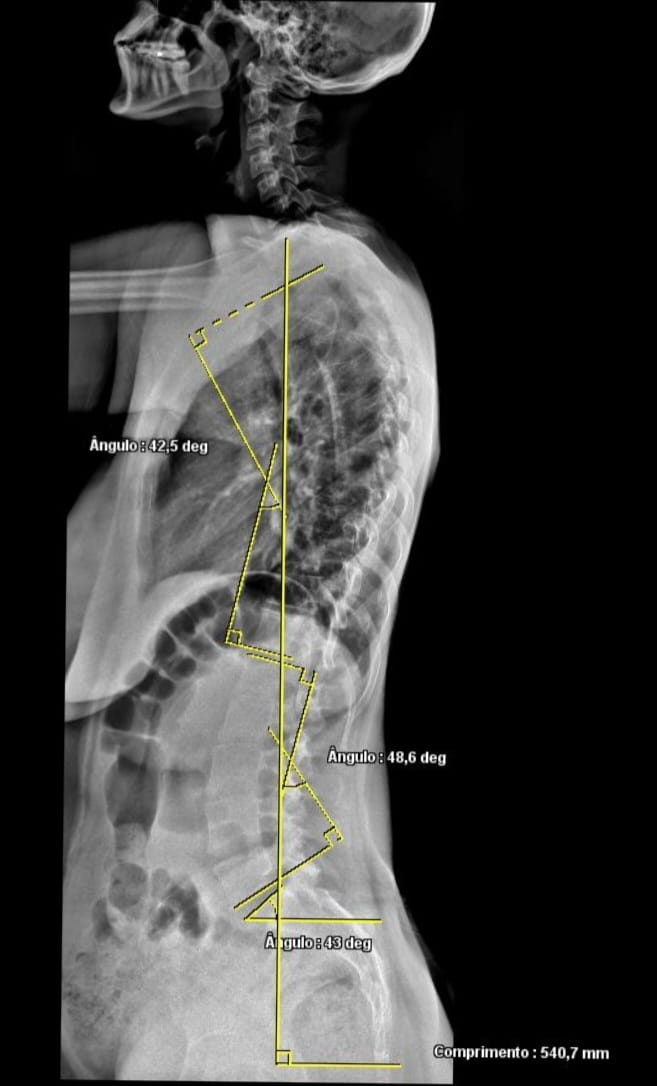

HSJ conta com atendimento de Raio-X completo de coluna para tratamento de escoliose

O HSJ agora conta com atendimento completo de Raio-X de coluna, auxiliando no diagnóstico e acompanhamento da escoliose com mais precisão e qualidade.

Com exames mais complexos e tecnologia avançada, o hospital amplia seus serviços para oferecer mais segurança, agilidade e cuidado para pacientes de Maravilha e toda a região.